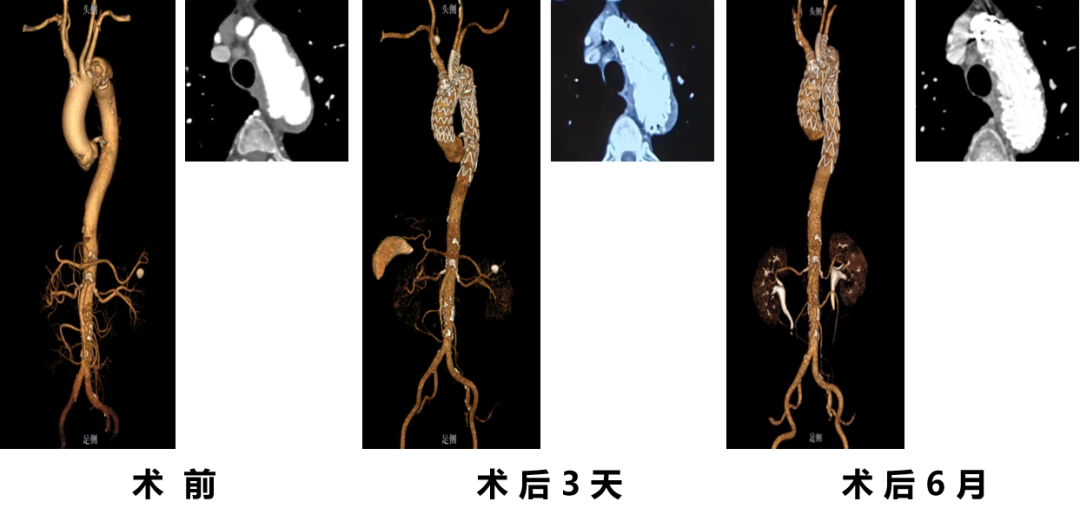

★ 病例2:模块内嵌分支胸主动脉覆膜支架系统

术前

术后